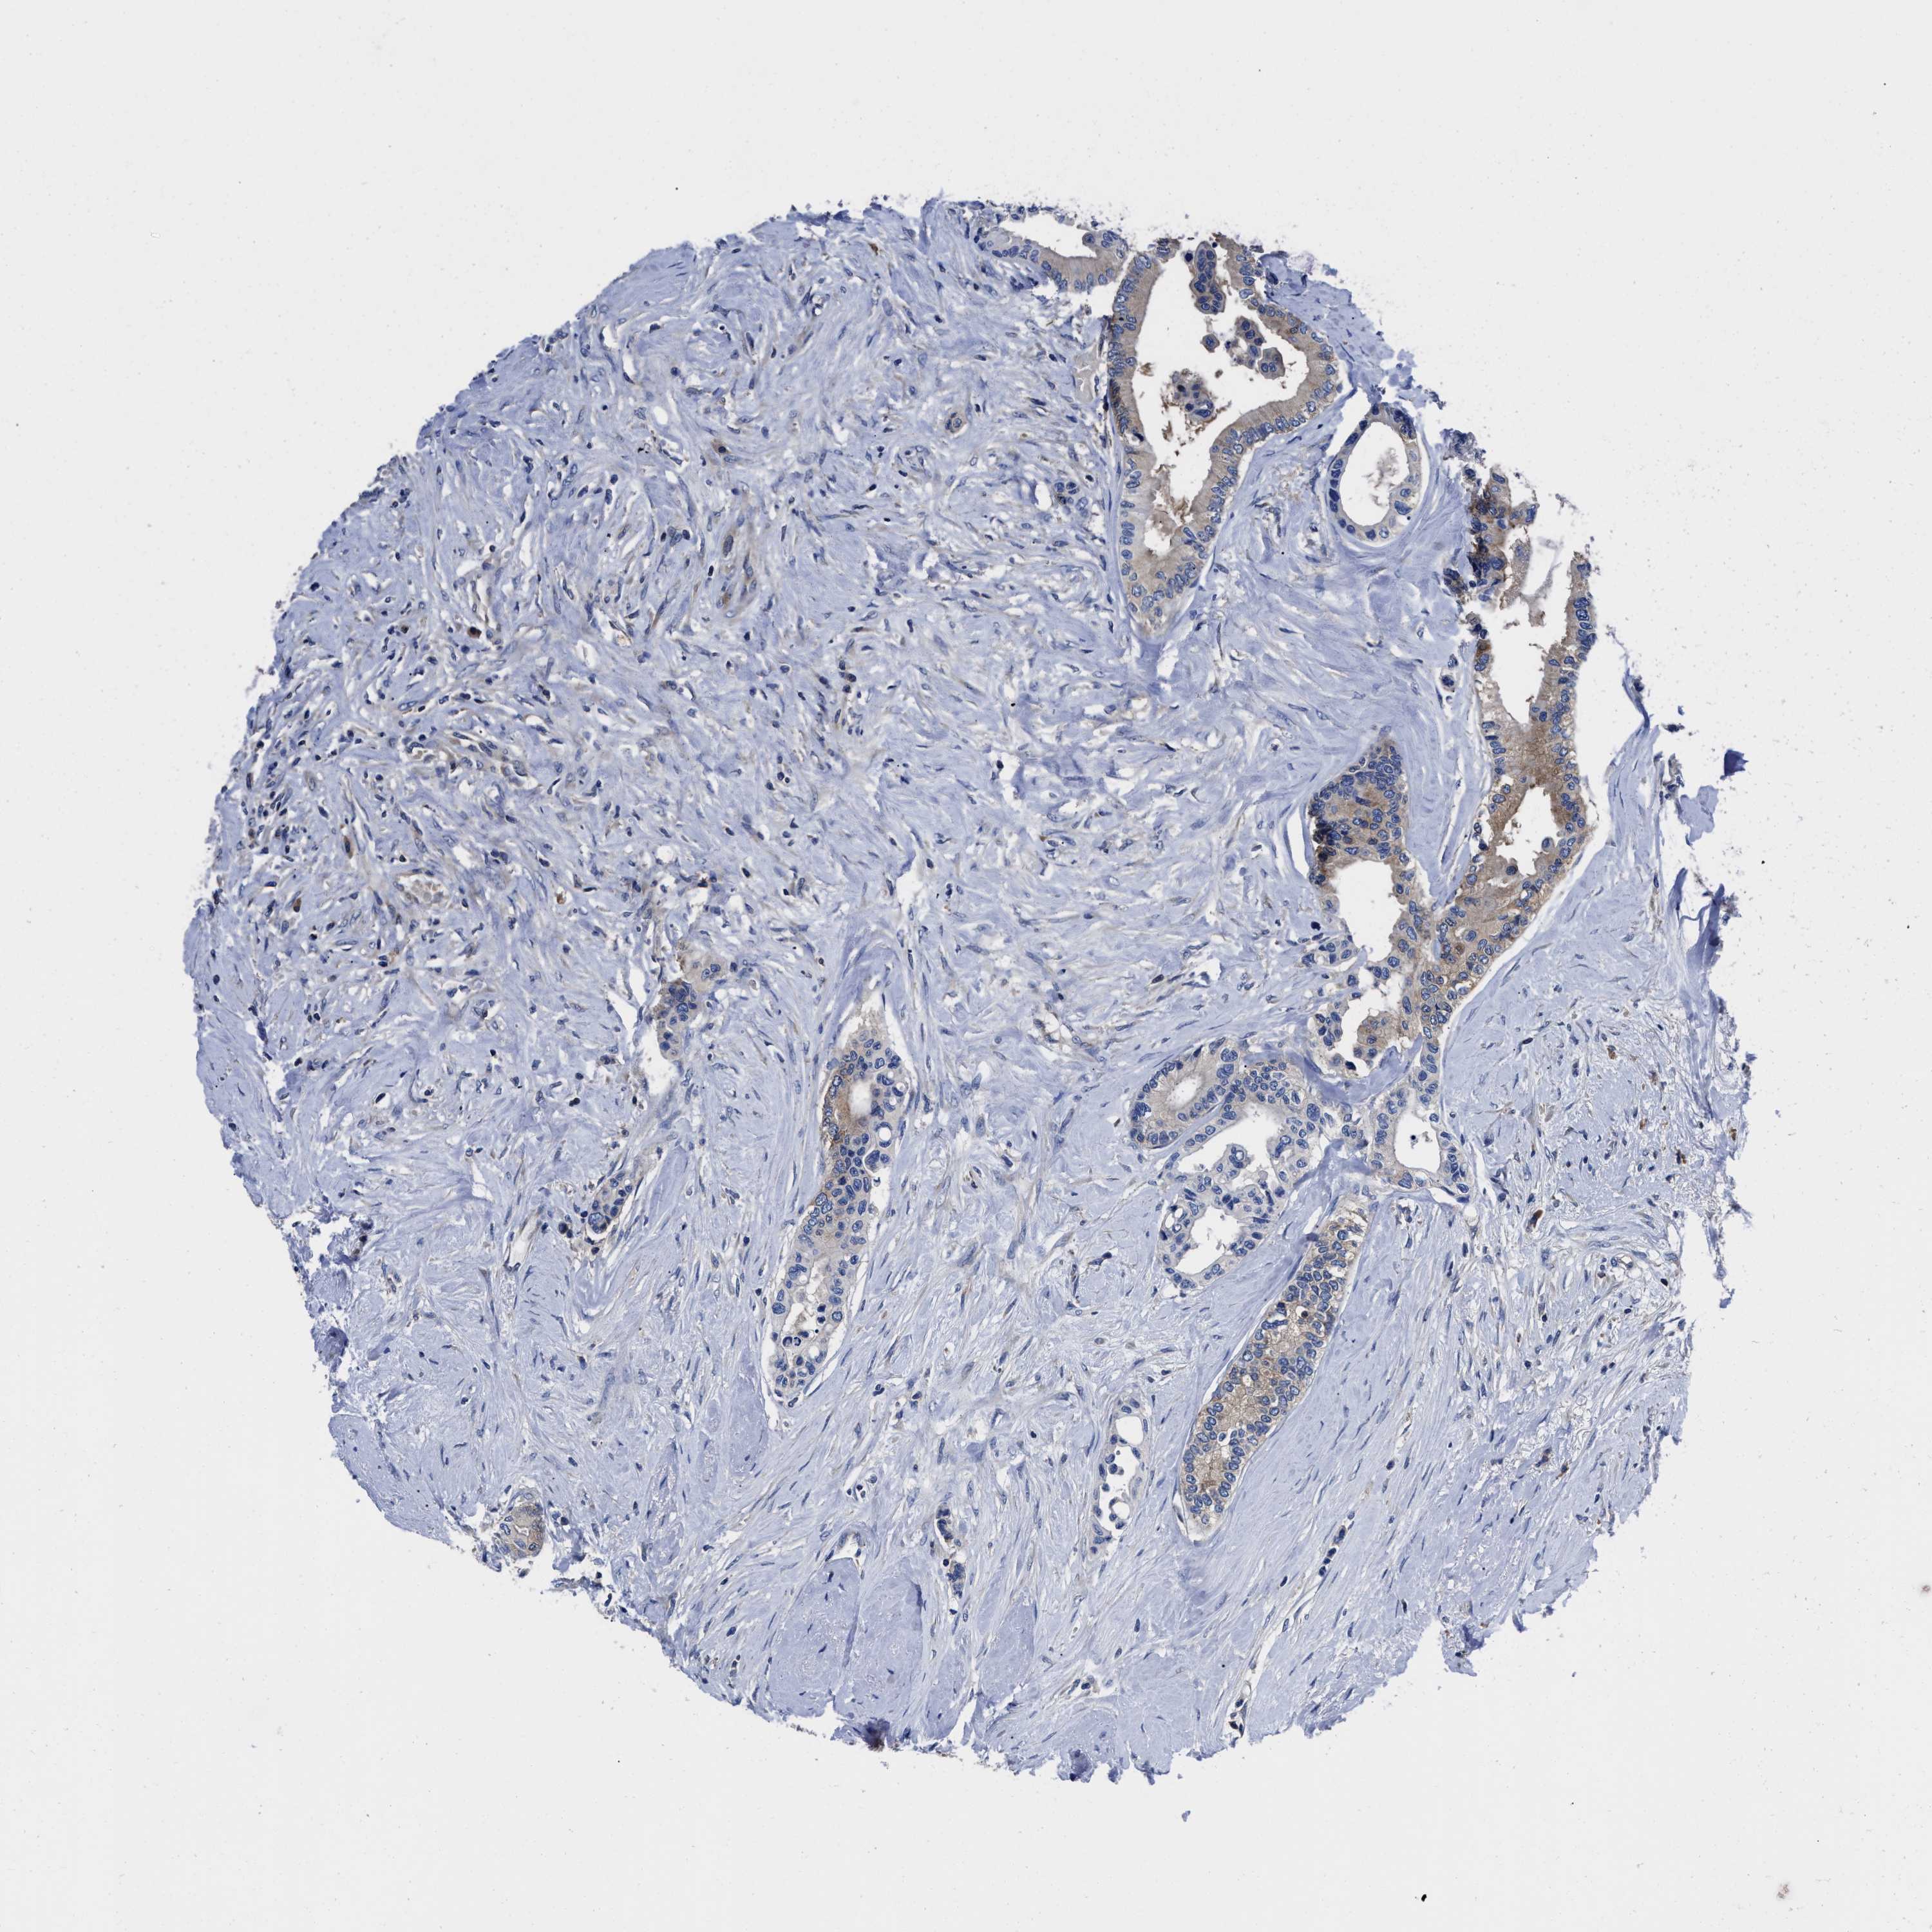

CANCER COLORECTAL CANCER Show tissue menu

Colorectal cancer

Human cancer

Colon adenocarcinoma